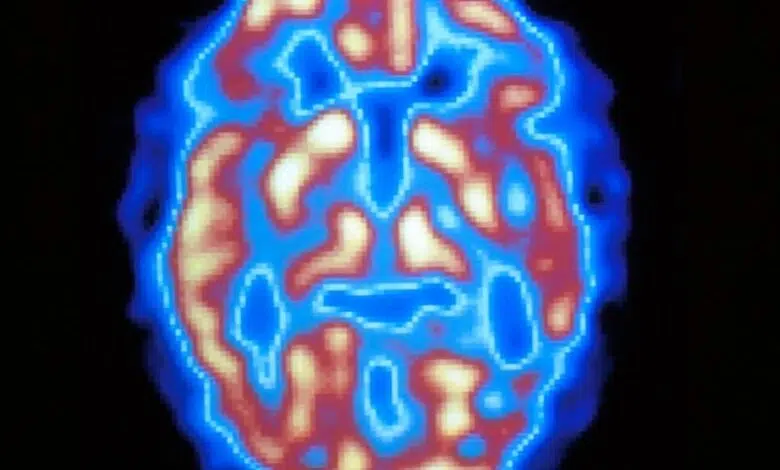

Investigadores de la Universidad de California en San Francisco ahora han entrenado con éxito un algoritmo de inteligencia artificial para identificar uno de los primeros signos de la enfermedad de Alzheimer, una disminución en el consumo de glucosa del cerebro, en imágenes de tomografía por emisión de positrones (PET). Según el estudio, el algoritmo predijo con precisión el eventual diagnóstico de Alzheimer en casi todos los casos de prueba.

En las imágenes PET, se ingieren o inyectan pequeñas cantidades de compuestos radiactivos en el cuerpo, lo que produce imágenes tridimensionales del metabolismo, la circulación y otras actividades celulares. El coautor del estudio, Jae Ho Sohn, radiólogo de la Universidad de California en San Francisco, dijo que la PET es ideal para una herramienta de diagnóstico de IA porque el Alzheimer provoca cambios sutiles en el metabolismo cerebral que ocurren años antes de que el tejido neural comience a degenerar. Estos cambios son «difíciles de detectar para los radiólogos», anotó.

El algoritmo fue entrenado y probado en 2100 imágenes cerebrales PET de aproximadamente 1000 personas de 55 años o más. Las imágenes son de un estudio de 12 años que siguió a personas finalmente diagnosticadas con Alzheimer, así como a aquellas con pérdida leve de memoria y controles sanos. El algoritmo se entrenó en el 90 % de los datos y se probó en el 10 % restante. Luego se volvió a probar en un segundo conjunto de datos independiente de 40 pacientes monitoreados durante 10 años. El algoritmo fue tan sensible que pudo identificar, en promedio, el 81 por ciento de los pacientes en el primer grupo de prueba y el 100 por ciento de los pacientes en el segundo grupo de prueba que serían diagnosticados con Alzheimer seis años después.Los hallazgos fueron publicados en febrero en radiología.